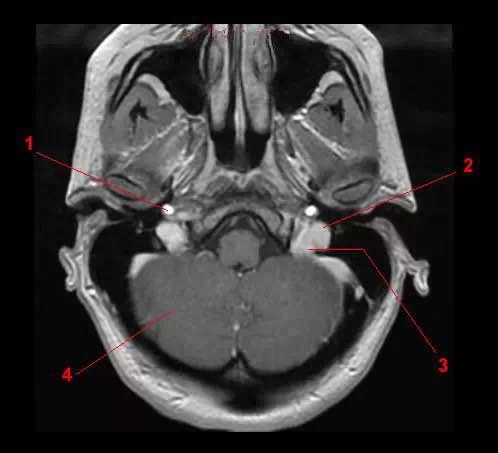

图5 颈内静脉(断面观)

图6 颈内静脉和椎静脉(磁共振断面)

1.颈内静脉;2.鼻咽;3.颈内动脉;4.小脑。